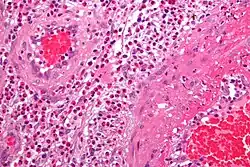

Pathologie

Feingeweblich zeigt sich eine starke Vermehrung eosinophiler Granulozyten im Gewebe (Gewebseosinophilie), mit Befall vor allem der kleinen Blutgefäße (mit Zerstörung, Blutgerinnselbildung und daraus resultierenden Infarkten). Daneben kann die Entzündung auch direkt auf verschiedene Organe übergreifen, z. B. auf das Herz mit der Folge einer eosinophilen Herzmuskelentzündung.